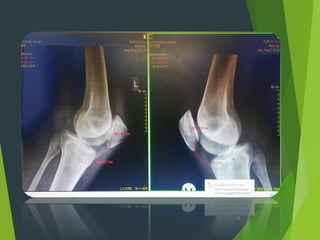

Lateral view

Crossing

sign

Insall-Salvati index:1.15

Right Left